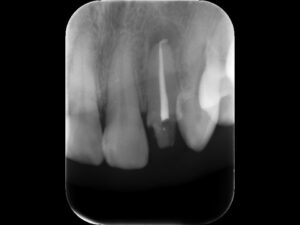

再根管治療後レントゲン。バイオセラミックとガッタパーチャによる根管充填を行った。根尖部まで緊密に薬が入っているのが分かる。このようにしっかりと根管治療を行うことで、安心して歯を被せることが出来る。